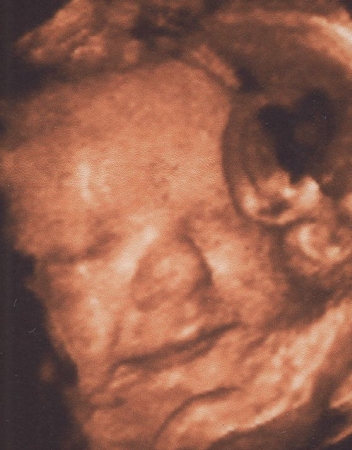

Kis tömzsi,golyó fejű az én édes kisfiam! :P

Bdp:10,13 cm; ofd:11,63; hc:34,78; fl:7,1; ac:33,1

Egy kicsit rövid a lába,de hát mi sem vagyunk óriásiak! :P

Méhlepény II.fokban érett,elegendő magzatvíz.Fejjel lefelé van törökülésben.Jaaaj nagyon jó volt látni!....és amikor ránk mosolygott... :oops: :P

Nagyon tetszenek a képek. 4D tényleg olyan, mintha egy fénykép lenne, teljesen felismerhetőek a vonások! És szerencsétek is volt, hogy ilyen rendes babó, és megmutatta az arcocskáját. Most megint ott vagyok, hogy nem baj, ha pici, de én MOST szeretném picikémet nézegetni!

Peti baba olyan jól látszik a képeken! :) Tényleg szerencsétek volt, hogy mindenét meg tudtátok nézni! Na, és a súlyáról nem írtál! Vagy csak én olvastam felületesen? Buksinak sincs hűű de hosszú lába, neki 6,95 mm-t mértek! :D És már csak 2-t kell aludni és itthon van Hábi!!!

a képek nagyon szépek :wink: Nagyon szépen látni Peti baba arcát :D